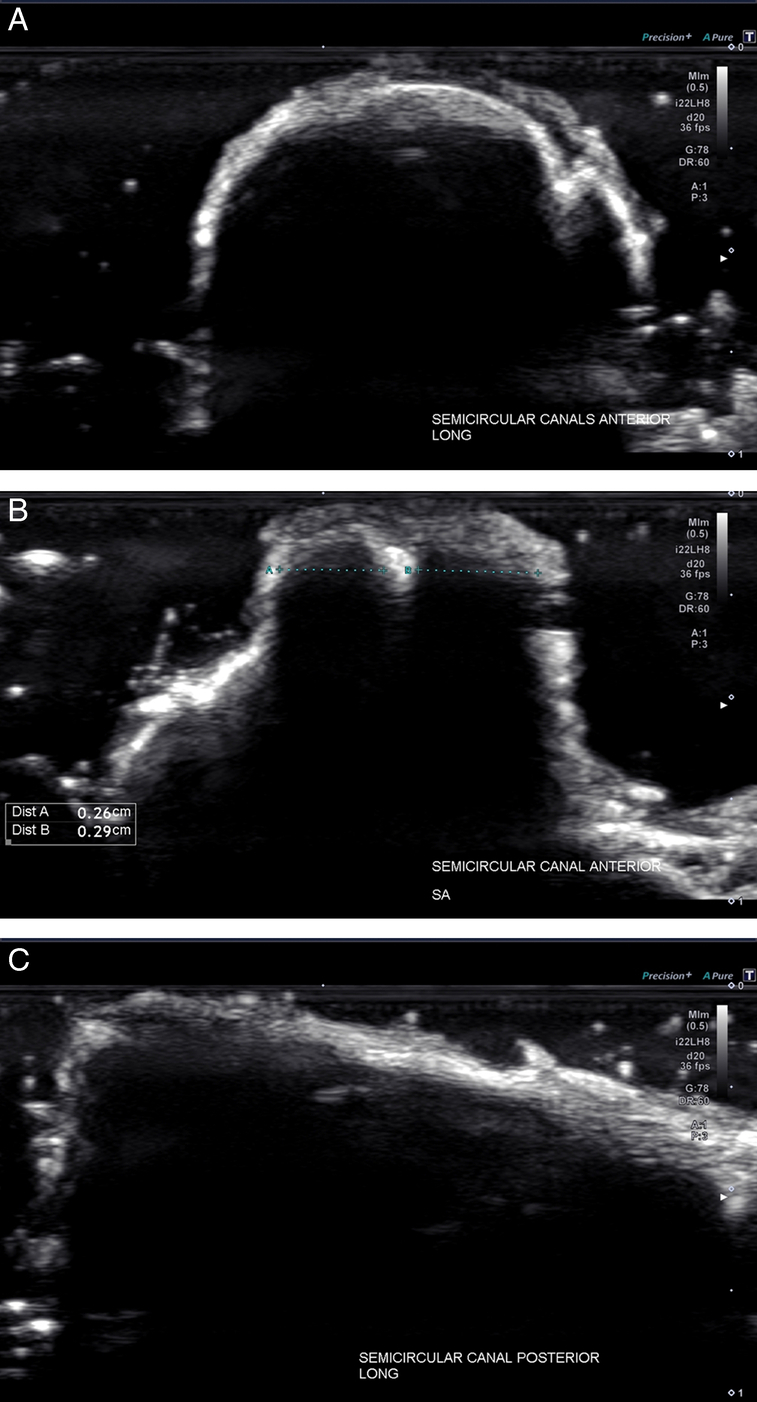

Results: The images were best optimized with 17 MHz and 22 MHz small footprint transducers. High-frequency ultrasound (US) images of the semicircular canals, vestibular and facial nerves, and utricles with reflected otoliths (otoconia) were obtained and reported in this article. Detailed visualization of both the vestibular nerve and facial nerve was accomplished, including identification of fascicular architecture. In addition, US reflection from the otoliths contained within the utricle was identified with sufficient clarity to provide surface measurements. Bony acoustic landmarks of the middle ear bones were identified by scanning externally from the tympanic membrane, including the dynamic movement of the bones with manual manipulation.